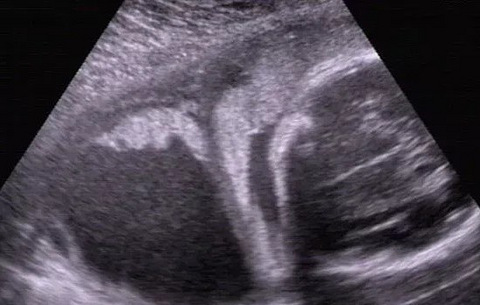

看到一个医生分享,希望这个妹子能够别放弃。刚遇到一件有点难过的事,有位刚30岁的年轻女性,可能永远没法当妈妈了。她从青春期月经来的次数很少,经量也少,本来想去医院查一查,可后来学习压力就顾不上了,再加上村医说孩子还在发育,不用担心,所以就没有好好检查过。结婚后两年多她没怀孕,才想起来到医院好好查一查。我安排她检查后诊断子宫小,幼稚子宫,子宫内膜薄(5mm左右),看双侧卵巢未见异常。她这种情况属于幼